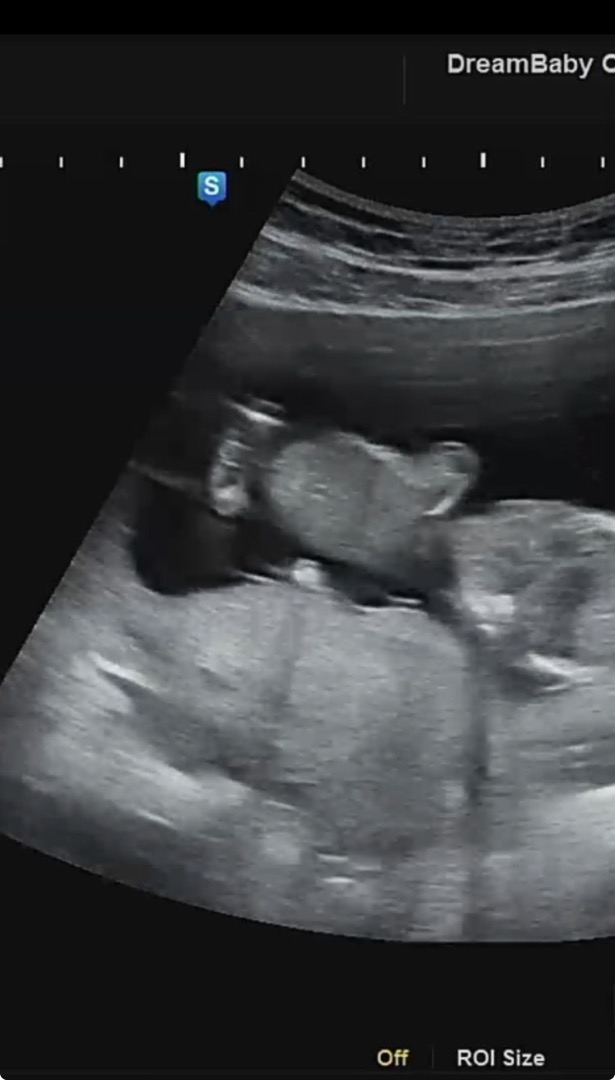

이게 복숭아일까요 고추일까요..?

현재 13주에요! 원래는 다음진료때 성별보러 가기로했었는데 오늘 입덧약 처방받으러간김에 아가 잘 있나 봤거든요! 그런데 헉 저건무엇..? 많은의견부탁드려요!!